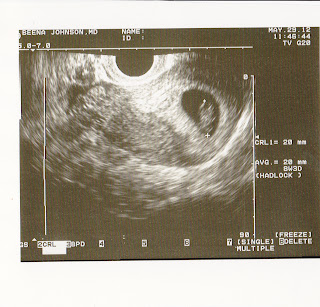

Monday 5/21/2012 Today was amazing! I anxiously awaited the 1:00 appointment to see my little bean. Praying for a little beating heart. I see the sack, and the doctor moving the wand around to get a good look and then I saw it, the little flickering bean!! Measuring 7 weeks and 1 day. 2 days ahead of what I thought I was. Not a big difference, but still 2 days further along means 2 days closer! Gave me my official due date of January 4, 2012! I love that Claire was due 1 day after my birthday and this little one is due 4 days after Eric's and 3 days after my Mom's! December is full and I do mean full of Westerman birthdays. So if it comes early there is no telling who it might share a birthday with. I really like the doctor I am seeing. She is being extra precautious with me. Told me I could still work out, but to walk or use the elliptical. No running which is a bummer, but I will do whatever to ensure this little one's safety. She also knows how nervous I am about everything and said she would see me once a week for as long as I want! Wow! So for now I will get to go in once a week to check the litte bean's progress! Oh I almost forgot to mention. When I was pregnant with Claire I never got sick, not even nausous. Oh ,but let me tell you this one is completely different! I have been so nausous on top of having a UTI and I just feel blah. But I don't care. I count my blessings to have the little one.

Tuesday May 29,2012. My flickering bean is now a flickering teddy grahm. It's really cool to get weekly scans and see the amazing difference 1 weeks makes in it's growth. Its unbelievable that the little bean now has little stubby arms and legs and a definite head! Measuring 8 weeks and 2 days! What's cool is I have an ultrasound of Claire at the exact same time so I had fun comparing the 2 photos. Doctor told me that at 11 weeks I go could off the Progesterone. I'm excited to be off of it, but nervous as well. She assures me that the placenta will be starting to work by then. Going back in a week to check progress again. I love seeing the little one and checking on it weekly, but I know God has his hand on this baby.

I've now seen my flickering bean turn into a teddy graham and now at 11 weeks into a little alien ;-). I call it my alien because it looks alienish with it's little eyes staring right at me. Oh how I love this baby. Claire is always amused with my weekly appointments. I tell her she will see the baby in Mommy's tummy on the screen. Sometimes she pays attention other times she plays her games on my iPhone. The doctor assures me the baby looks amazing! Yolk sac is still there, but could see the placenta forming. Another anterior placenta like with Claire. No big deal just means I will feel the baby later.

The following 3 pictures are weeks 9, 10, and 11.